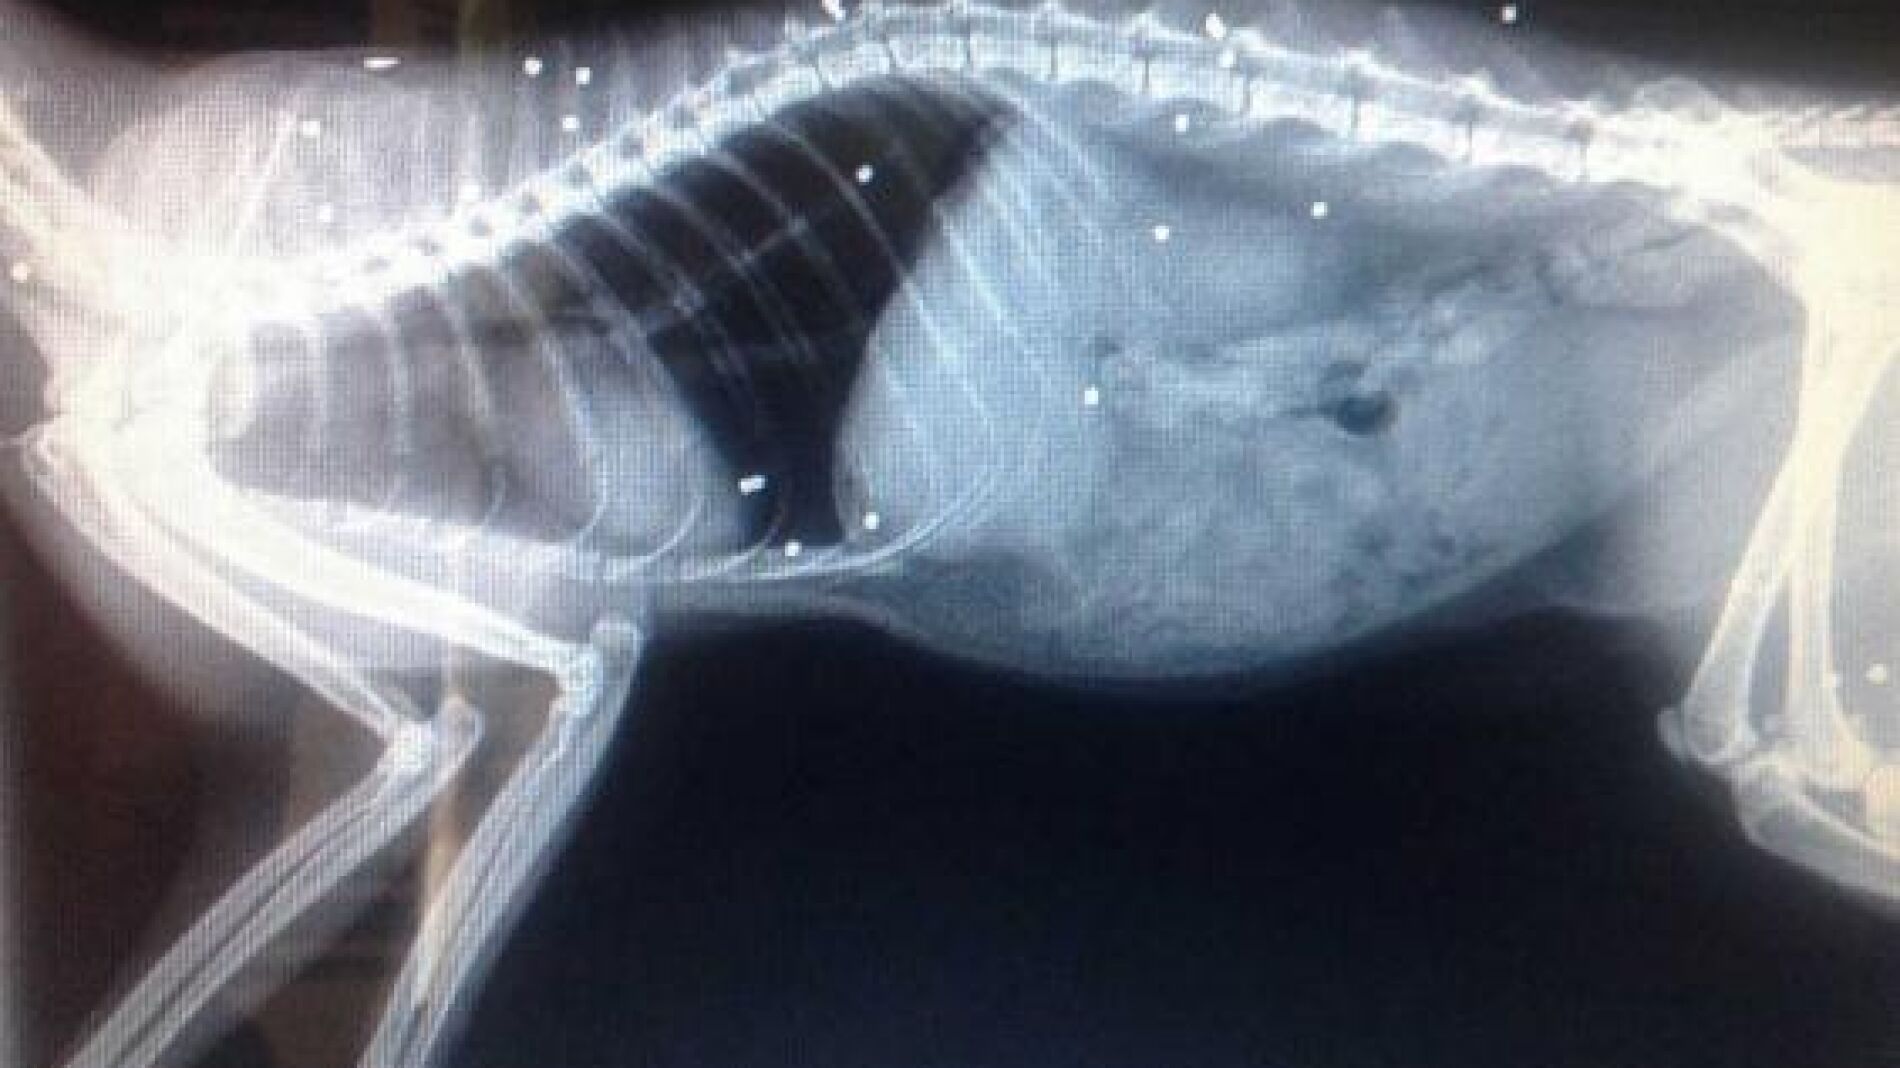

Fue llevado a un veterinario donde fue examinado con rayos X. La radiografía reveló que su cuerpo estaba repleto de perdigones.

Según informa el diario británico Independent, el inspector Adam Jones ha asegurado que tendrán que extirparle el ojo al gato debido a que "una bala impactó en el centro de su ojo causando un desprendimiento de retina". Ha añadido que "le es complicado caminar debido a otra bala en una de sus patas.

Por su parte, el veterinario ha señadado que otras dos balas impactaron en su médula espinal dañándola de forma seria, y que por tanto, "es un milagro que haya sobrevivido".